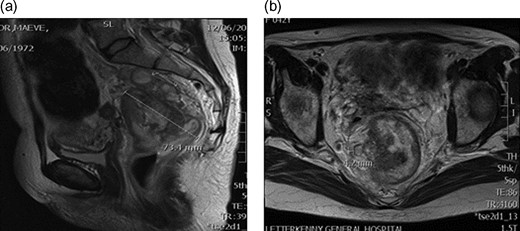

A 43-year-old female, 10 weeks postpartum, underwent colonoscopy for bleeding per rectum showing a bulky tumour (Fig. 1) in the rectum at 5 cm. Histologically poorly differentiated adenocarcinoma of the rectum (Fig. 2) T3N1Mo. Underwent laparoscopic loop ileostomy formation for impending bowel obstruction. Bloods showed Hemoglobin13.6 g/dL, Bilirubin 10umol/L, CEA 3.6 ng/mL. MRI pelvis (Fig. 3a and b) showed locally advanced annular neoplasm of mid and upper rectum. CT TAP (Fig. 4) reported no distant metastasis. She had neoadjuvant chemoradiothreapy with poor response. Post chemotherapy she noticed a lump in her right breast and axilla. Breast mammogram (Fig. 5a) showed 26 mm lesion in the right breast at 10 o'clock position and ultrasound showed 27 mm lesion in right axilla. Core biopsy (Fig. 6) reported signet ring morphology. The tumour stained positive with CK20, CDX-2 and CEA. There was no staining with CK7, ER, PR or Her-2. The rectal biopsy specimen, also analysed for KRAS status, was KRAS/NRAS/BRAF negative. She is being followed up by oncology with FOLFOX+Panitumumab.

(a) MRI pelvis showing rectal tumour 7.3 cm two lymph nodes. (b) MRI pelvis Mucinous component within 5 mm of the right meso-rectum.